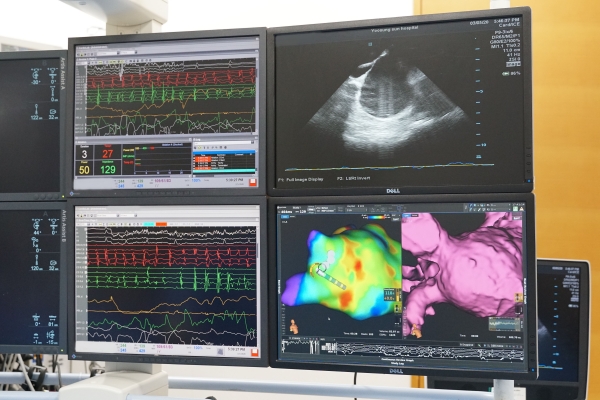

리드미아는 심방세동의 근본적 치료법인 전극도자 절제술 시행 전, 심장에서 발생하는 전기 신호를 감지해 원인 부위를 3D 고화질 영상으로 등고선 같이 보여준다. 전극도자 절제술을 시행하려면 이 매핑 과정을 반드시 거쳐야 한다.

리드미아에는 △생체전기 임피던스(신체에 미세한 전류를 통과시켜 정보를 얻는 방법)와 △마그네틱 트래킹(신체에 자장이 형성되고 전극도자 끝에 센서가 부착되어 도자 위치를 파악하는 기술) 2가지 기술이 함께 탑재돼 있어 기존의 매핑 시스템보다 해상도가 높고 해부학적 구조가 세밀하다.

특히 리드미아와 함께 사용되는 오라이온 카테터는 심장 내부의 전극 신호를 얻어 원인 부위를 찾는 데 기존 시스템보다 25배 이상 정밀하다. 정밀한 시스템 덕분에 원인 부위를 모두 보여줄 수 있고, 원인 부위에 정확히 접촉해 해당 부위를 빠르게 괴사시킬 수 있으며, 부정맥 유발 가능성이 높은 잠재적 원인 부위도 시술 할 수 있다.